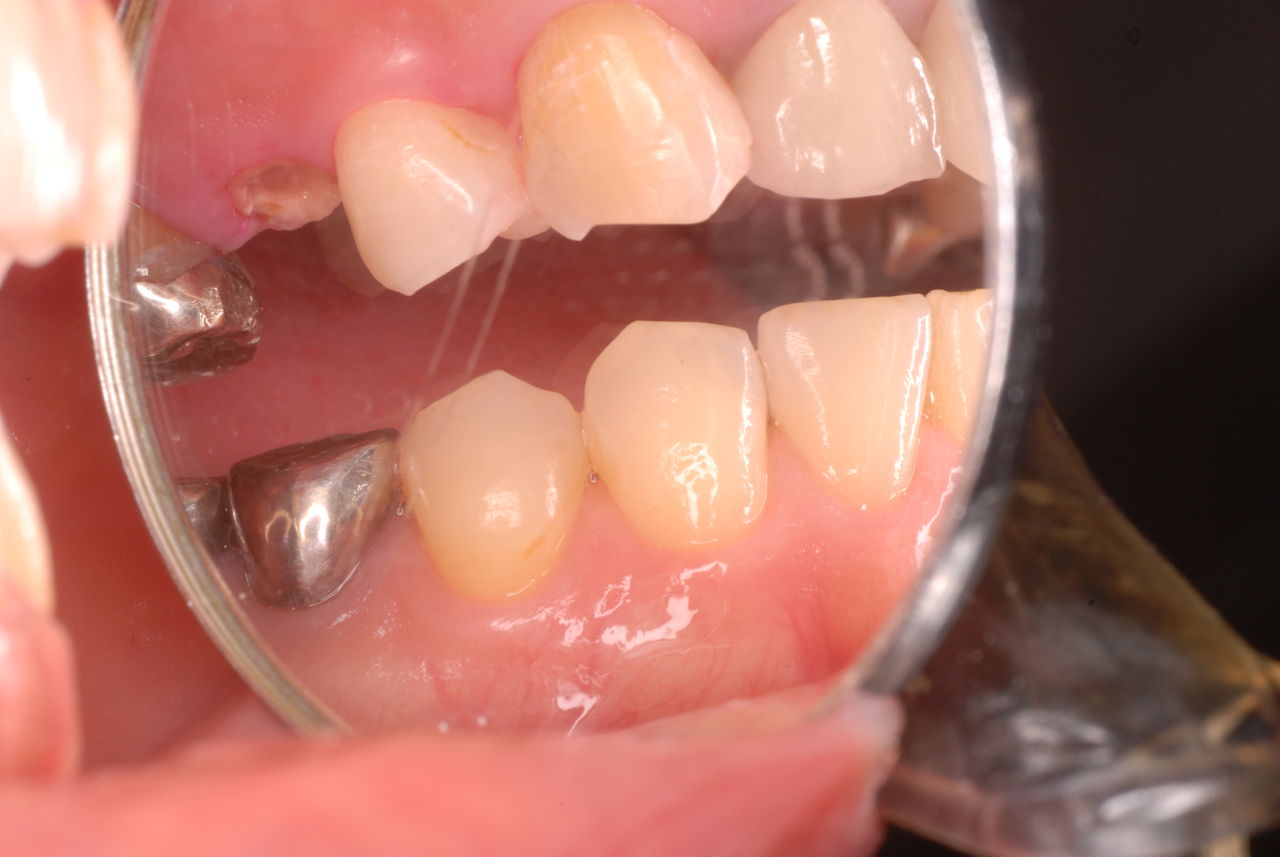

写真左下の親知らずが痛くなり抜歯しました。その後歯茎を除去して虫歯を露出させる処置を二回ほどしています。